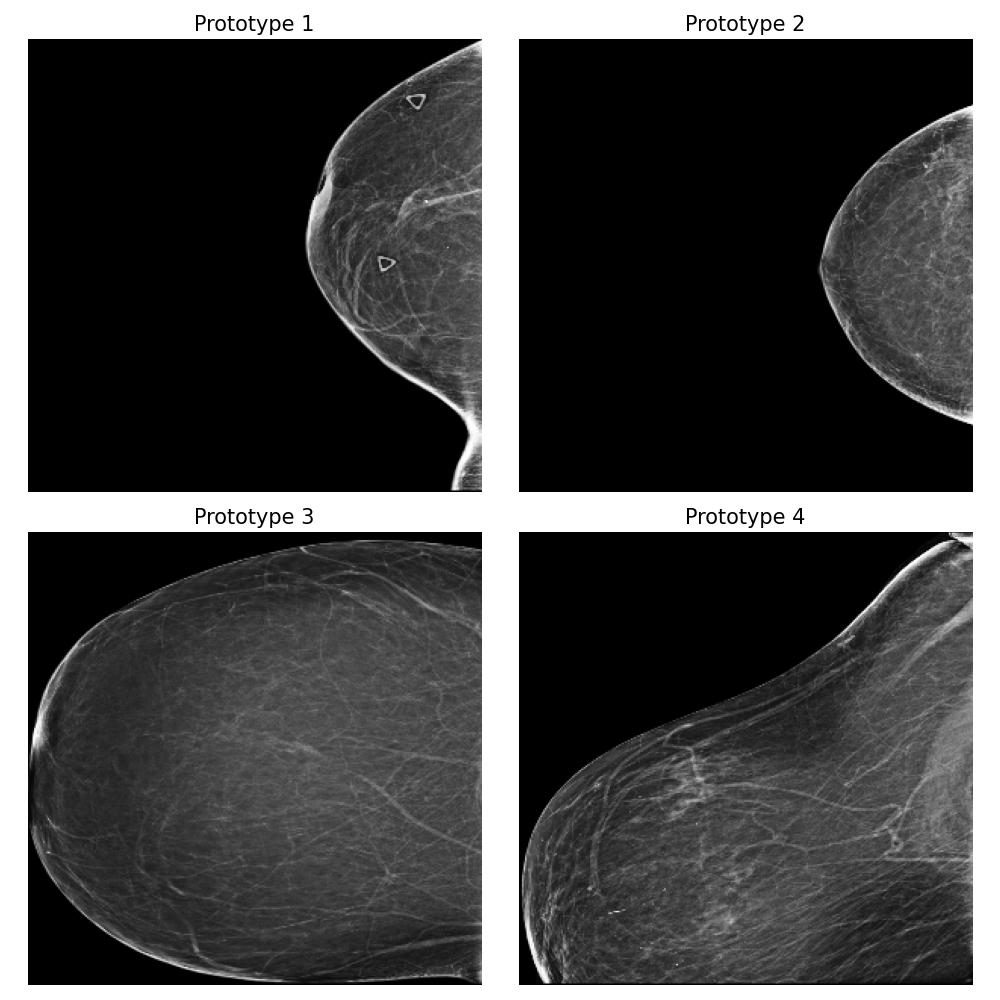

Dataset and

We use the publicly available EMBED dataset (Jeong et al., 2023). To simulate premenopausal and postmenopausal patient populations, we construct two datasets, and , by randomly sub-sampling from EMBED. Dataset comprises 27,224 mammograms from 8,456 patients with dense breast tissue (density category three in EMBED) and 21,675 mammograms from 7,841 patients in density category two. Dataset includes 27,224 mammograms from 2,715 patients with less dense tissue (density category one) and 21,675 mammograms from 7,797 patients in density category two (medium density). All mammograms were preprocessed to remove clinical markers and aligned such that the breast tissue faces left.

For this task, we implemented the “Prototype-summarization-based explanations” described in Section 3.5. We trained a binary vs classifier using the VGG19 feature extractor as backbone and learn four prototypes for each dataset. 97798 mammograms were used for training, and 24450 mammograms were used for testing.

Result

By examining the summarization prototypes shown in Figure 22, we identified tissue density as the primary difference between and . In mammograms, brighter areas correspond to denser tissue. Additionally, we observed that less dense tissue is often associated with larger tissue size. Without our proposed method, human users would need to manually analyze the dataset, which is a labor-intensive and time-consuming task, to reach the same conclusions.

Robustness of the explanation

To examine the robustness of our explanation result, we repeat the explanation algorithm approach on bootstrapped versions of and . Five bootstrapped datasets were constructed by resampling by patients with replacement. As shown in Figure 35 in Appendix Section B.5, we reach the same conclusion for all the bootstrapped datasets.

Coverage evaluation

We again evaluate the coverage quality of the learned set of prototypes using the AUCC score. The coverage curve is shown in Figure 24. We also display the learned latent space for and in Figure 24 and the two datasets and the prototypes are well separated even though they contain overlapping mammograms with density category two (i.e. medium density breasts).